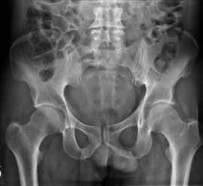

Figure 7Figure 7 is the pelvic radiograph of a 33-year-old man involved in a high-speed automobile crash. Examination reveals a blood pressure of 90/50 mm Hg and a pulse rate of 120/min. Radiographs of the chest and lateral cervical spine are normal. A CT scan of the abdomen does not reveal any intraabdominal bleeding. What is the most appropriate management for the pelvic fracture?